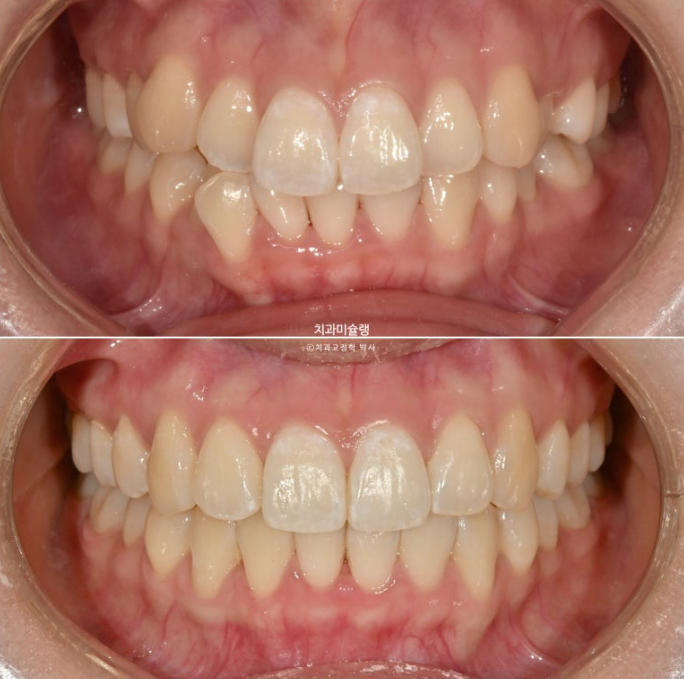

토끼이가 개선되면서 스마일라인이 조화롭습니다.

앞니각도는 깔끔하고

처음에 비하여 입이 나오지 않았습니다.

예쁜 입매도 잘 유지가 되었습니다.

치근흡수도 없고 치근평행도도 좋습니다.